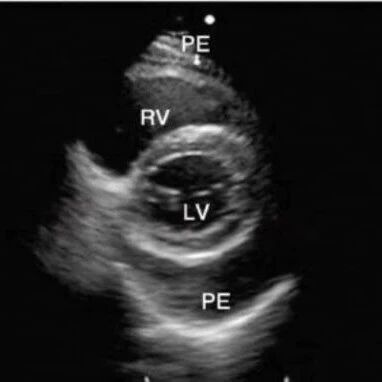

做题总是犹豫?ARDMS心超常见考点Pericardial Effusion完整解析!